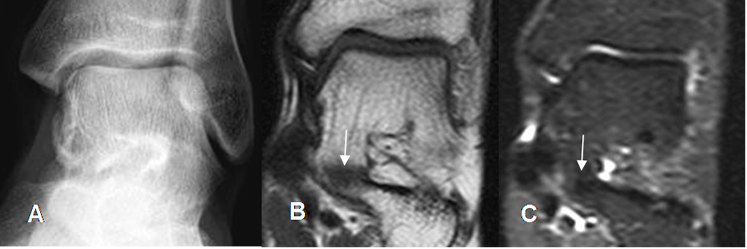

Fig 136 B. Coalición fibrosa del tarso.

A: Rx AP. No se encuentran anormalidades.

B: RM coronal en T1 y C: RM coronal en STIR. Unión en la parte interna de la

articulación talocalcánea mediante tejido conectivo, por coalición de tipo fibroso.